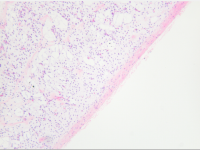

王功伟老师肾脏肿瘤系列讲座(十五):

王功伟

北京大学人民医院病理科